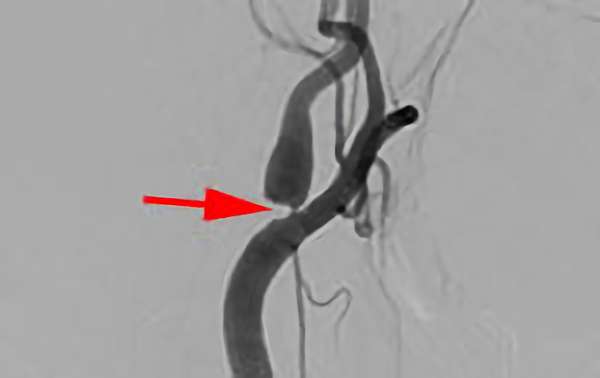

右内頚動脈狭窄症

大阪府の病院

No.859 手術前

No.859 手術中

No.859 手術後